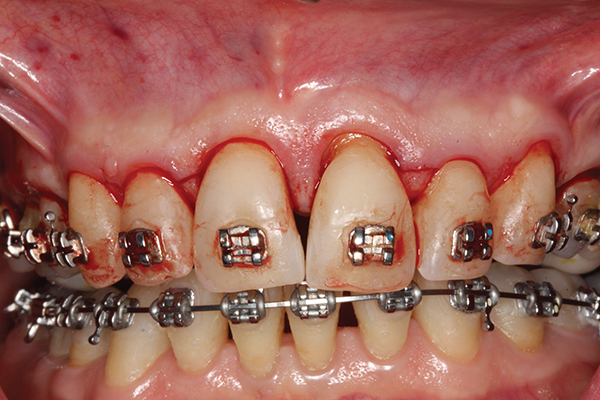

Fig 7. Preoperative CBCT 3D tooth position and regional bone anatomy. Note maxillary hypoplasia, malocclusion, and dentoalveolar deficiencies.

Figure 7

Fig 8. Preoperative CBCT 3D bone anatomy matched with postoperative CBCT final orthodontic tooth position. Note dental malocclusion correction

with significant detriment to the dentoalveolar bone. Orthodontic therapy would have exceeded the orthodontic walls and limits, causing

iatrogenic consequence.

Figure 8

Fig 9. Actual post-SFOT CBCT 3D tooth position with post-SFOT regional anatomy demonstrating alveolar augmentation

of the maxilla and mandible in conjunction with dental malocclusion correction. Dental malocclusion, dentoalveolar deficiencies, and

alveoloskeletal discrepancies have been addressed for comprehensive interdisciplinary management.

Figure 9

Fig 10. Lateral view of tension-free wound

closure. Note lower anterior augmentation gained to allow mandibular anterior teeth to be moved into new alveolar housing for optimal anterior protected articulation and interincisal and mandibular incisor angle position. Labial root torque was accomplished, which could not have been

performed without improved dentoalveolar bone volume.

Figure 10